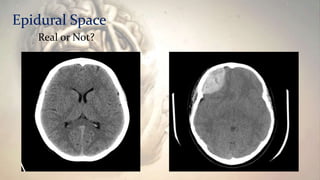

Epidural Space

Real or Not?

How to differentiate between Epidural hematoma

from other hematomas?

Clinical Manifestation: • Alteredconsciousness. • Headache. • Vomiting. • seizure. • Aphagia. Diagnosis • MRI and CT scan. Epidural hematoma as seen on CT scan with overlying skull fracture. Note the biconvex shape hemorrhage. Also some brain contusion with bleeding on the opposite side of the brain.